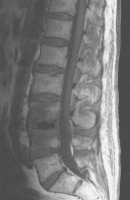

Abbildung 2: 1,5 Tesla, sagittale T1-gewichtete Sequenz nach Kontrastmittelgabe: Zustand nach X-LIF (am 5. postoperativen Tag) mit perkutaner transpedikulärer Stabilisierung bei L3/L4. Keine Kontrastmittelaufnahme der Wirbelkörper L3/L4 nachweisbar.